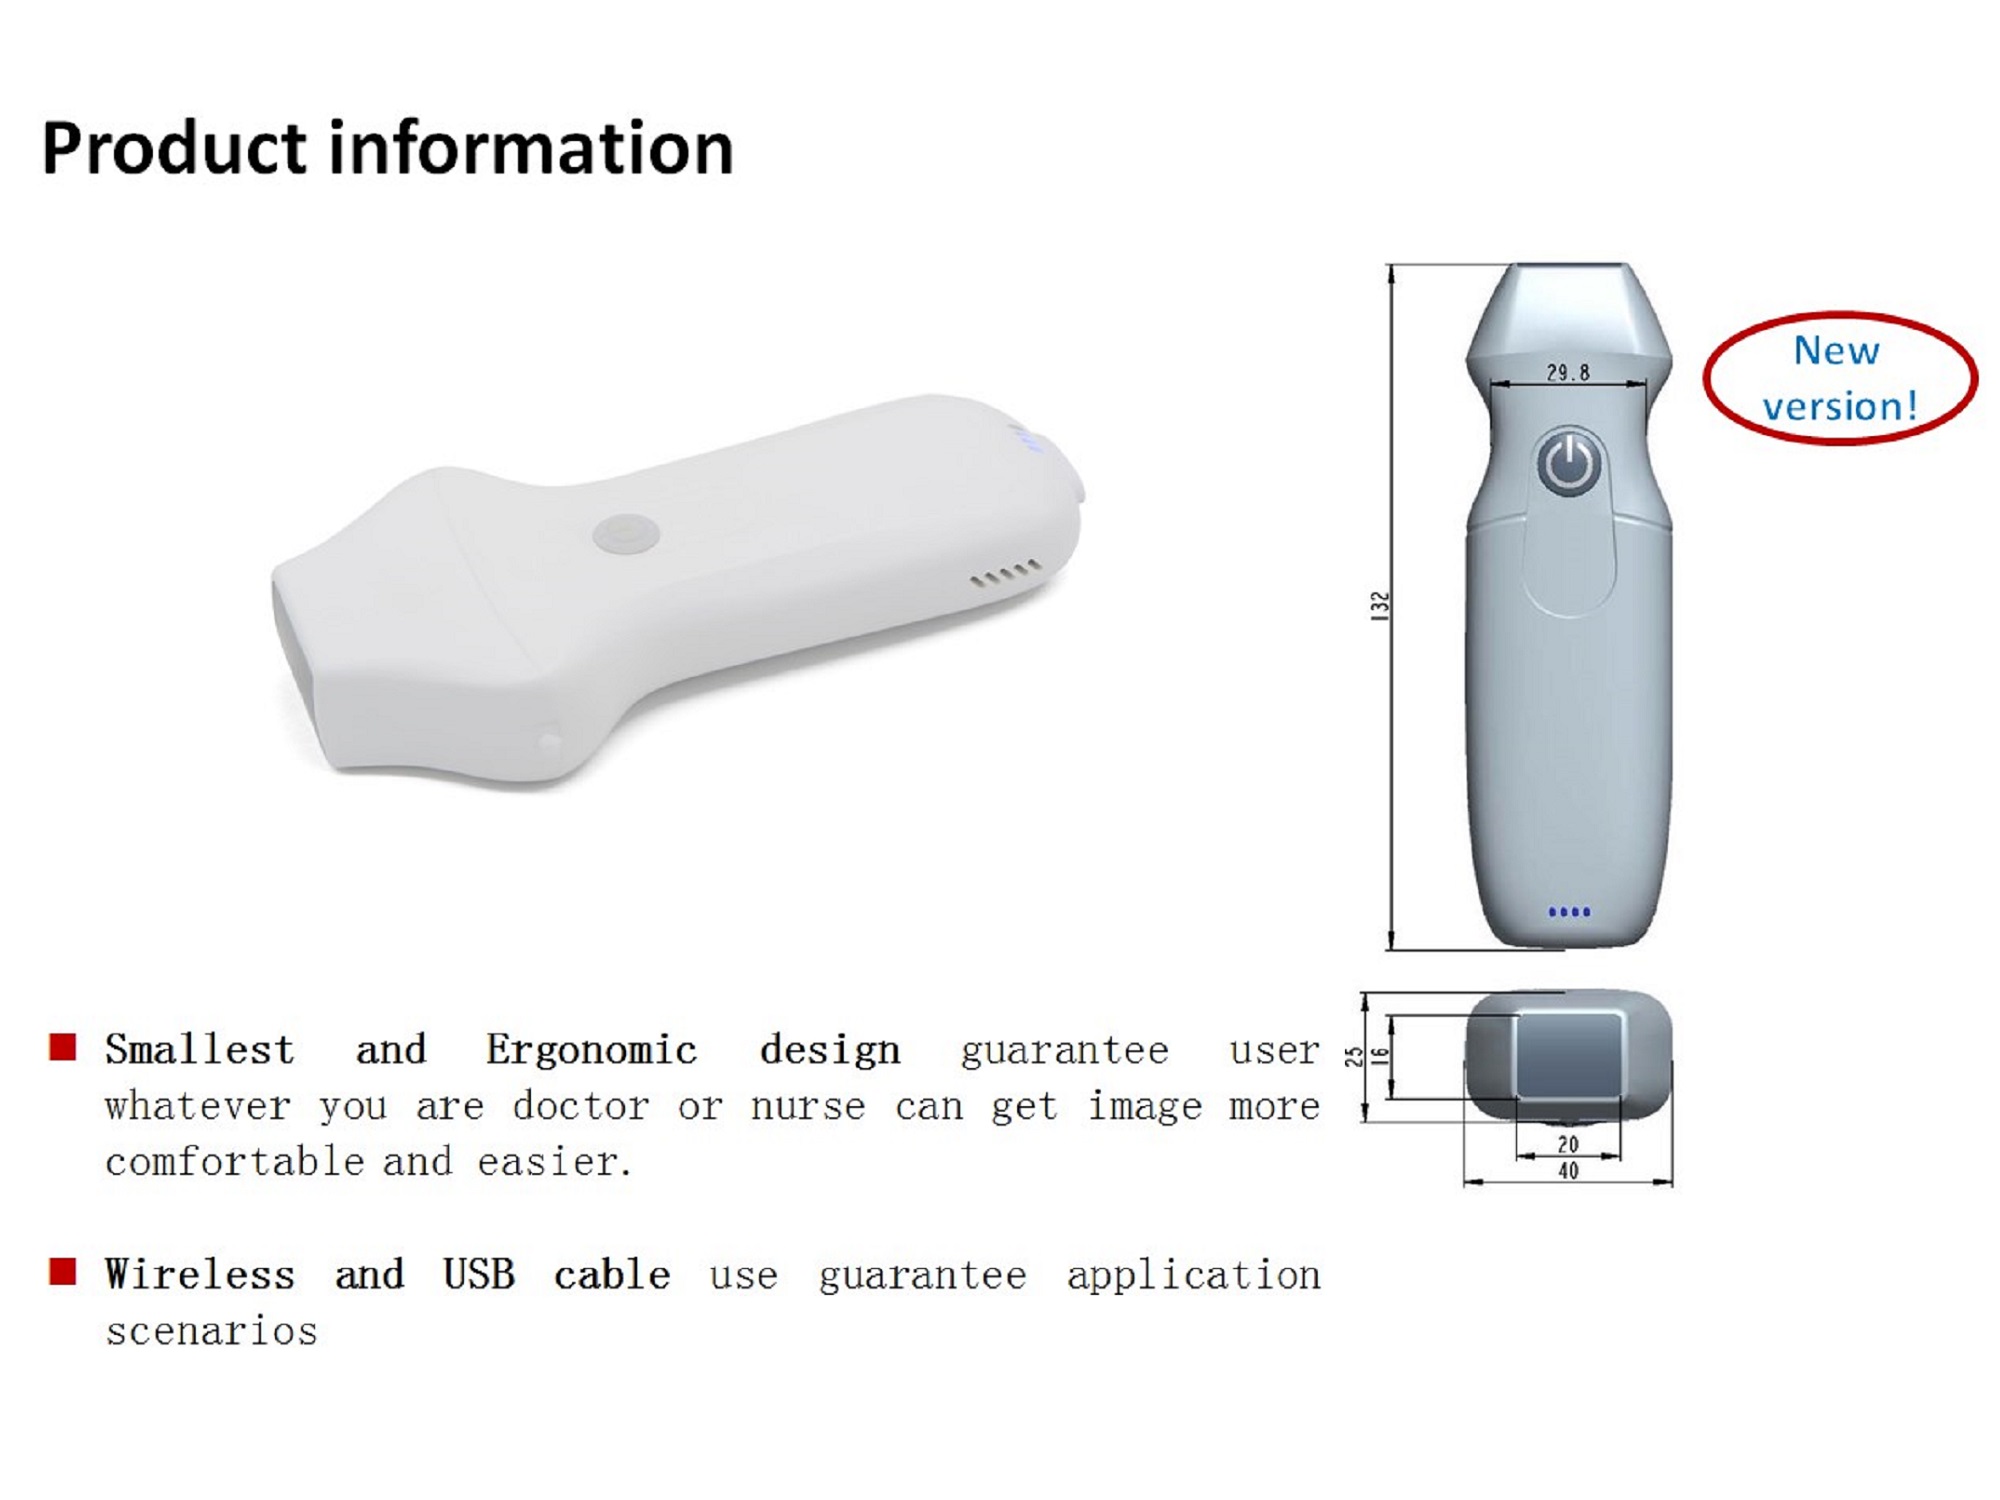

Dormed WiFi Probe Phased Array it’s an OEM Dormed Hellas portable Wifi probe which can connected with PC units, Tablets and Mobile devices with Android, Windows and iOS operating system.

Specifications

Channel of RT: 64

Display mode: B, B/M, and Color, PW, PDI

Frequency: central 2.8 MHz, cardiac harmonic 3.6 MHz, transcranial 2.5 MHz

Display Angle: 80°

Display Depth: 90/130/160/190mm

Image Adjust: Gain, DYN, Focus, Depth, Harmonic

Measure: Length, Area, Angle, Heart

Frame rate: 15~20 frames/second

Battery working time: 2 hours

Charge: by USB cable charger Type C

Working system: Apple iOS, Android, Windows

| Βάρος | 0.12 κ. |

| Διαστάσεις | 13.6 × 4 × 2.8 cm |